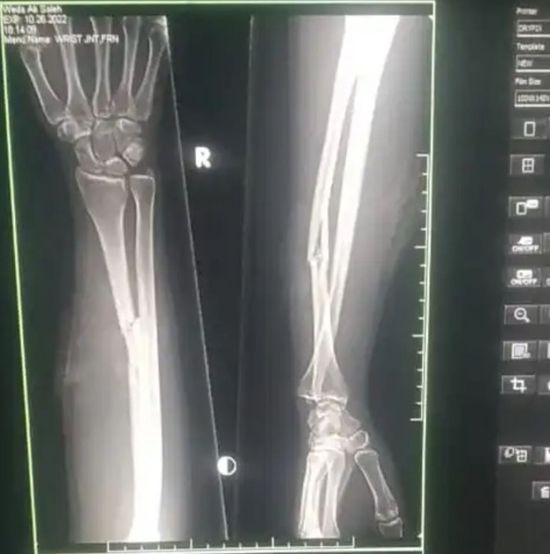

كشف الدكتور سميح حزام مدير مستشفى زايد الميداني بمنطقة سناح عن استقبال المستشفى الفتاة الجريحة باليد والفخذ جراء طلقتين من قناص حوثي.

وأشار إلى اكتشاف كسور في عظمة اليد وأعلى الورك، مؤكدا أن الضحية وداء محمد صالح البسيسي (20 عامًا) لا تزال ترقد في العناية المركزة.